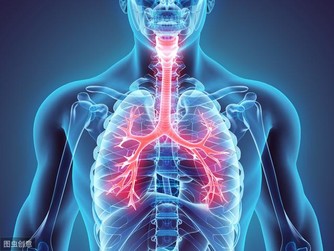

腎臟是主導我們身體毒素循環排出的一個重要器官之一,但是生活中很多人都會忽視其重要性,常常患有腎虛而不自知,久而久之給身體帶來了嚴重的負擔。